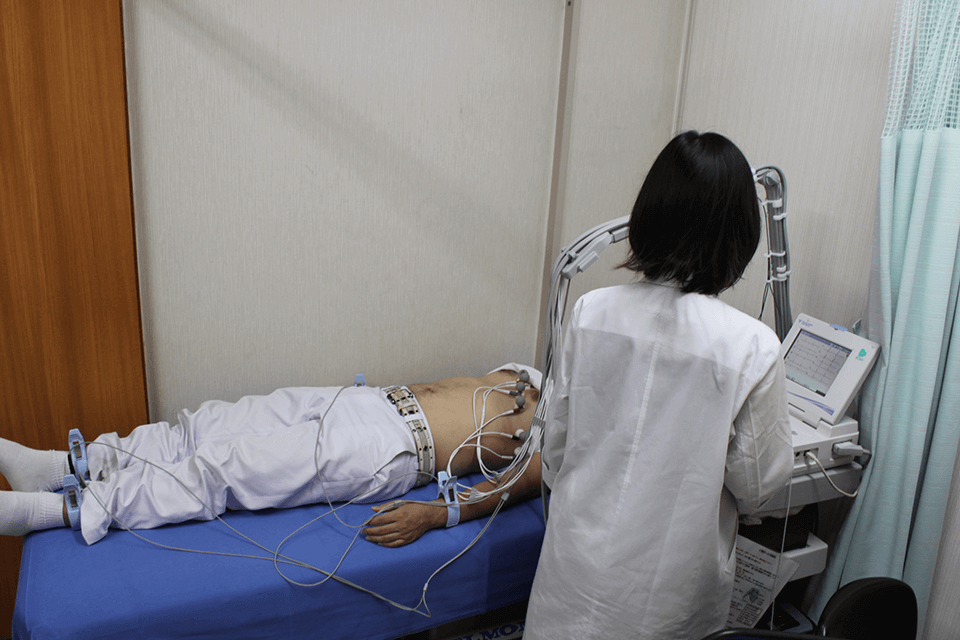

心臓が動く時に生じる微弱な電気信号を波形として記録する検査です。

胸と手足に電極をつけ、リラックスした状態で検査を行います。

種々の不整脈、心肥大、狭心症、心筋梗塞、電解質異常などの診断に役立ちます。